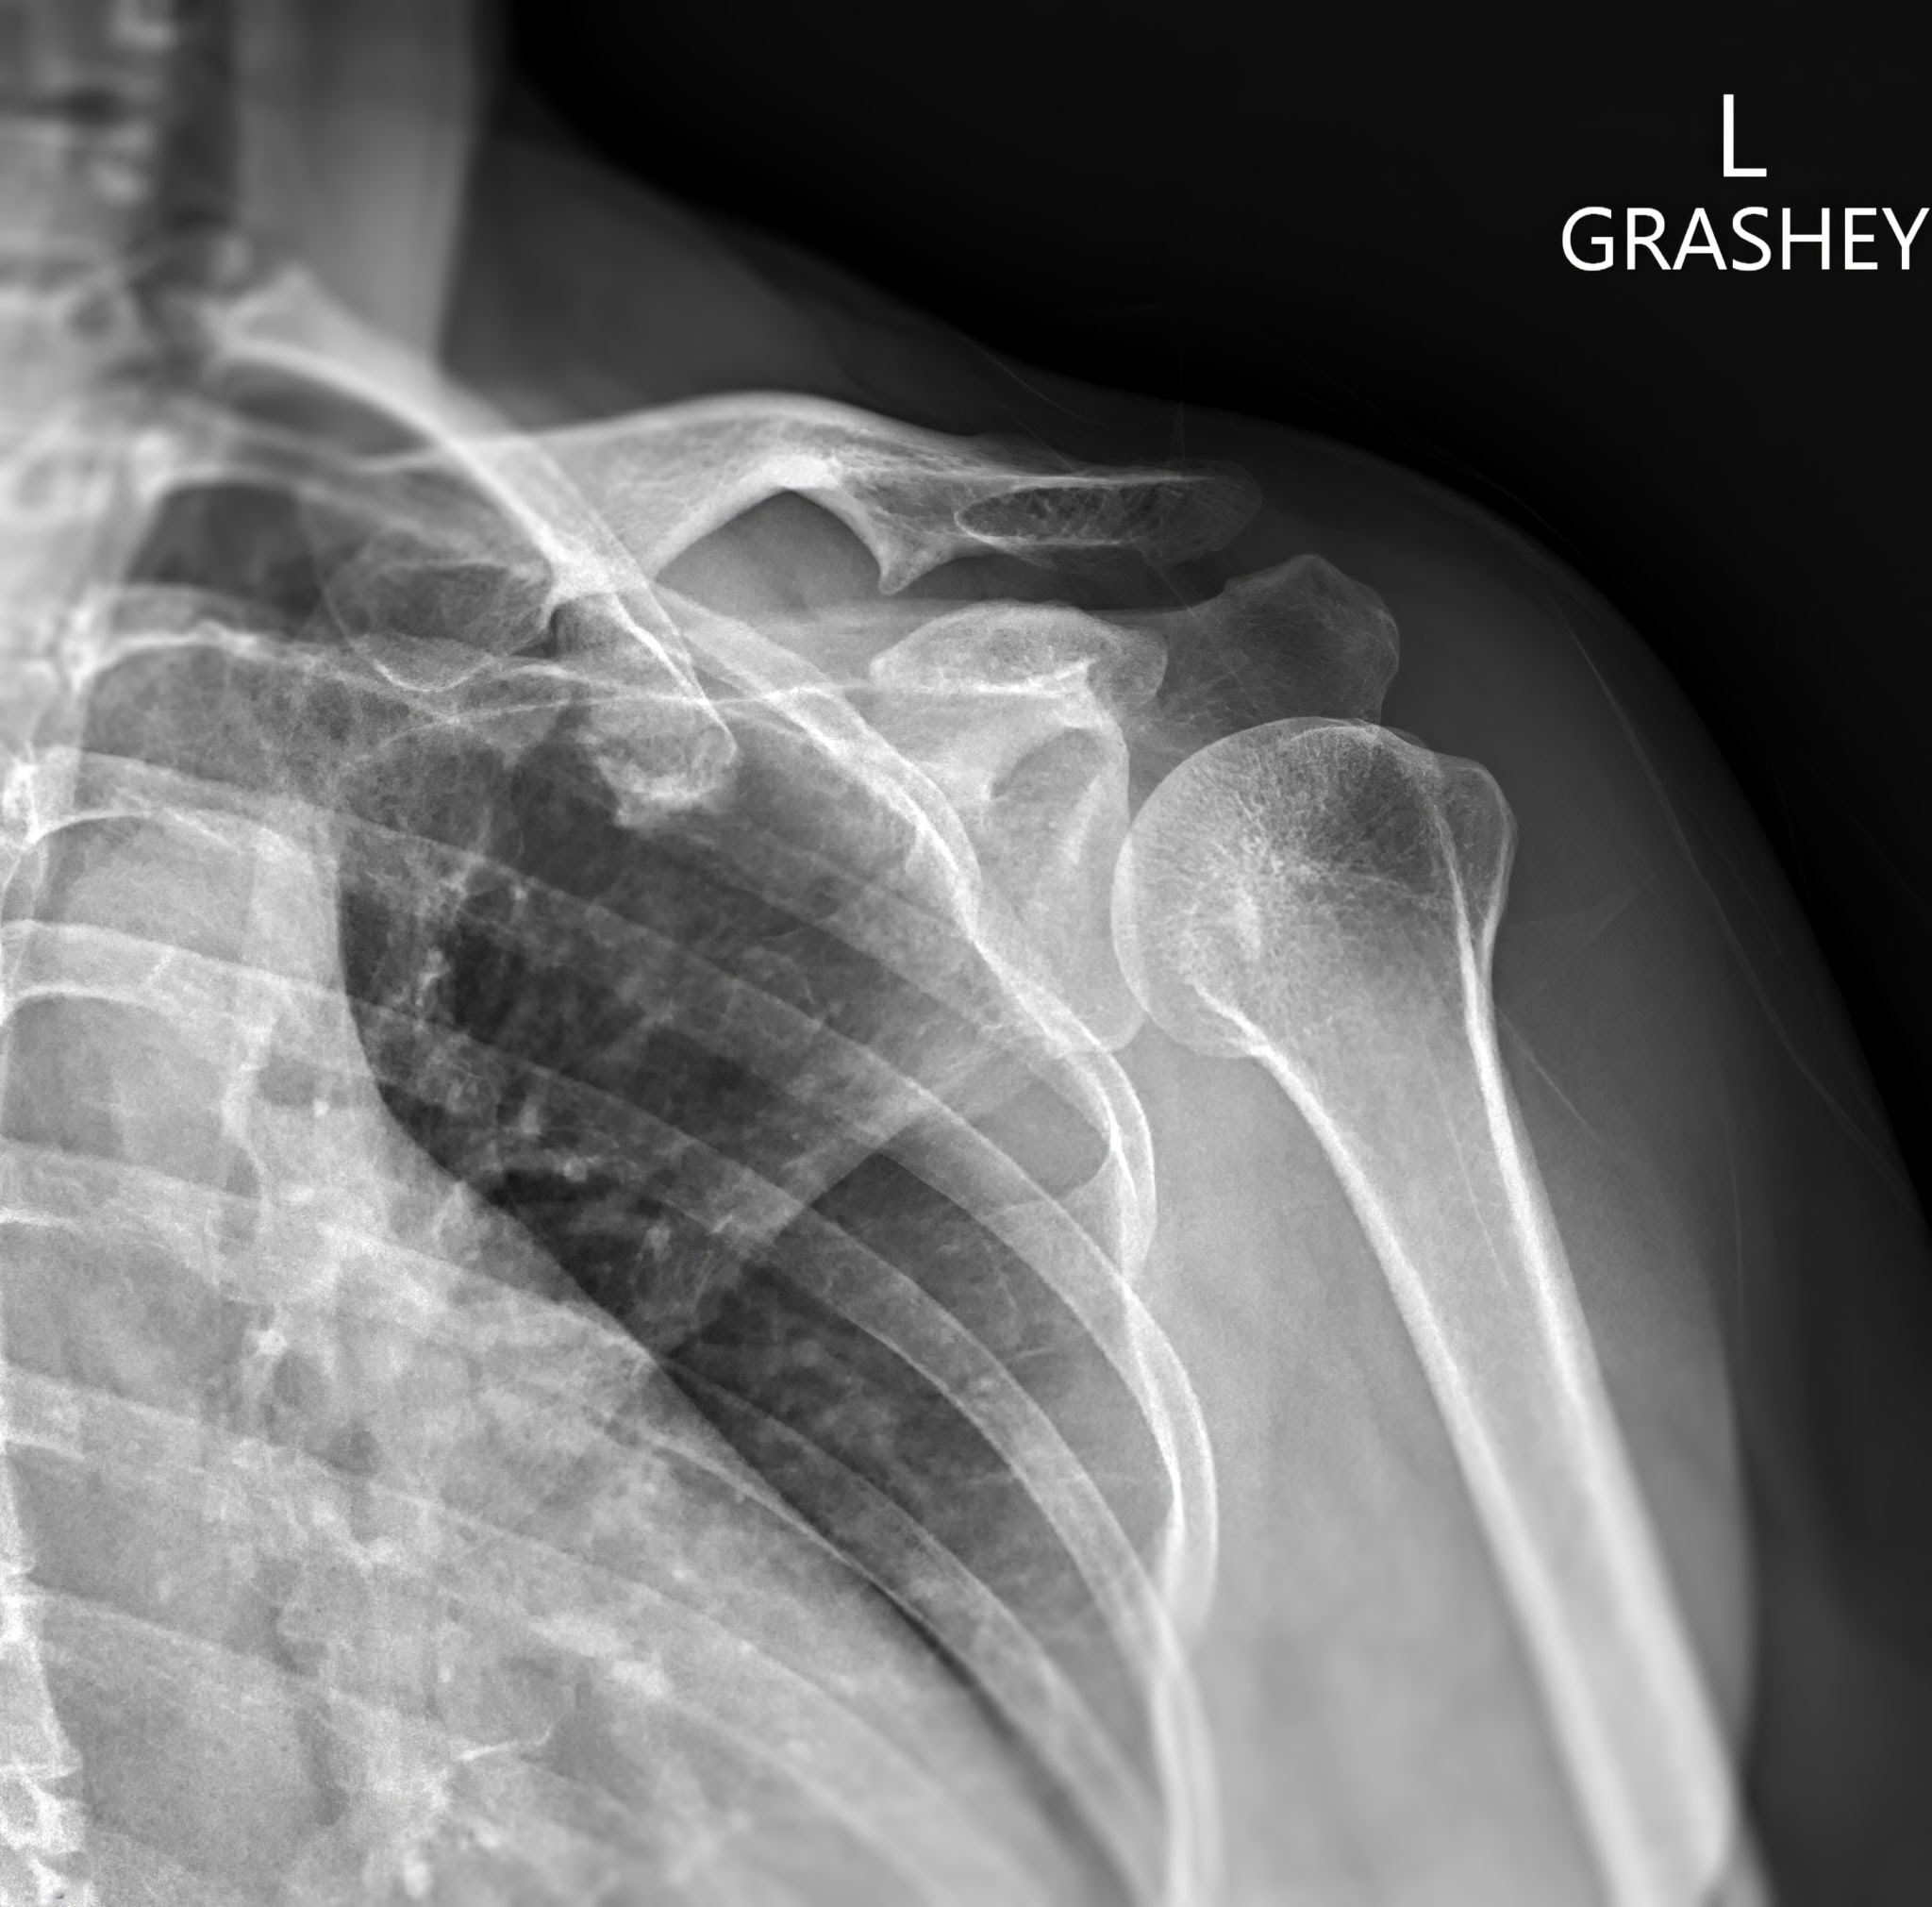

The Grashey View is a specialized X-ray projection used to provide a true anteroposterior view of the glenohumeral (shoulder) joint. In this view, the patient is rotated approximately 35° to 45° toward the affected side, aligning the scapula parallel to the image receptor. The X-ray beam is directed perpendicular to the shoulder joint space. This positioning eliminates overlapping of the humeral head and glenoid fossa, offering a clear view of the joint space, which is often obscured in standard AP views. The Grashey view is particularly useful for evaluating glenohumeral arthritis, joint space narrowing, fractures, and dislocations.

Grashey view